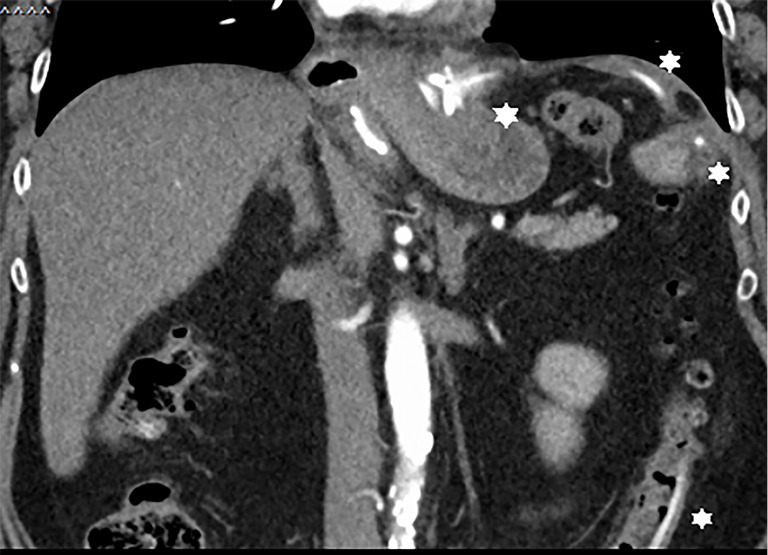

Case description: In our present case, we report on an asymptomatic patient with intraluminal penetration of the dislodged adjustment tube into the colon 26 years after implantation of a gastric banding system. We revealed the complication randomly by positron emission tomography-computed tomography (PET-CT) in the course of a tumor staging of a newly diagnosed lung cancer. The gastric band was removed laparoscopically, the adjustment tube however, had to be cut through due to extended adhesions and could only partially be removed. The rest of the catheter passed spontaneously via rectum on the following day.